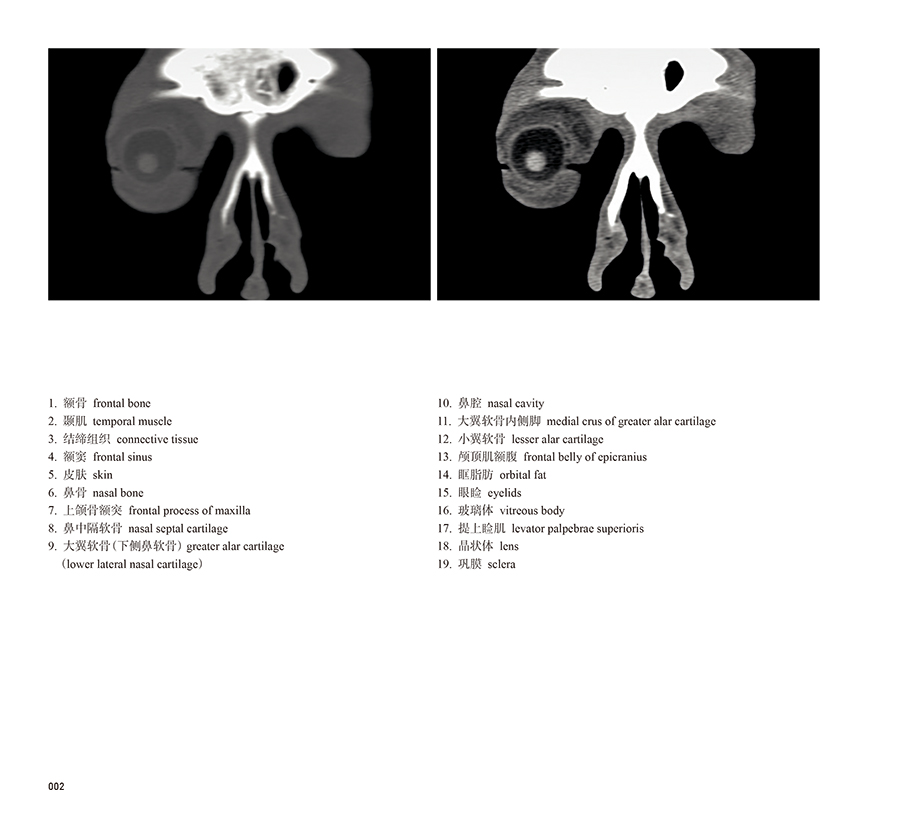

本书从数据集每隔1.2mm选取一幅图像,截取眼、耳、鼻及毗邻颅底的局部区域图像,共112幅图像。同时配以相应部位的CT图像对照。本书特色是断层解剖图利用数字图像处理技术优势,放大并清晰展示眼、耳、鼻及毗邻颅底断面的局部区域结构,组织色泽真实,甚至能够清晰显示肌肉纹理、筋膜纹路等细节结构,图像质量高于美国《人体断层解剖学彩色图谱》(引进版)类似图谱图像质量。对眼科、耳鼻咽喉科和神经内外科医生理解相关解剖结构有较大帮助。